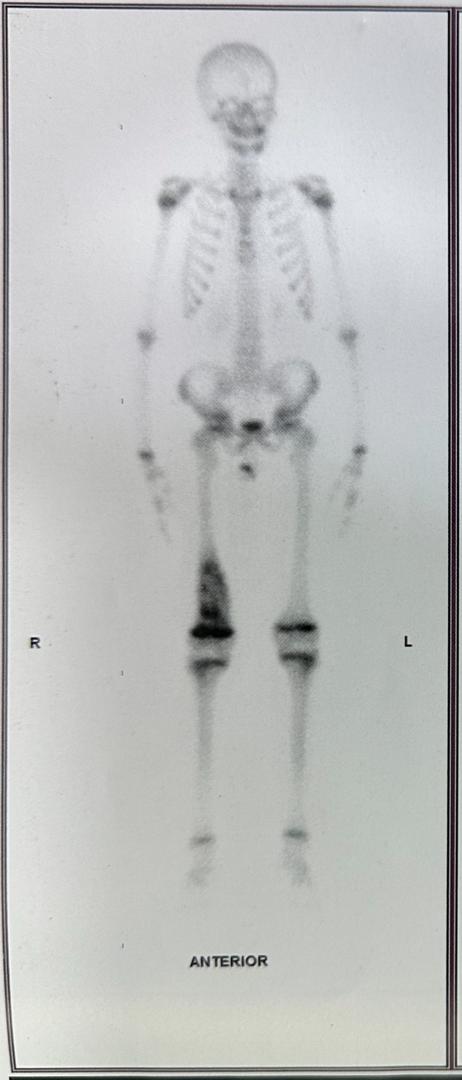

Les signes et symptômes du cancer des os commencent souvent dans un os. Ce cancer affecte principalement les os longs des jambes, et parfois ceux des bras. Les symptômes les plus fréquents comprennent :

- Gonflement autour d'un os.